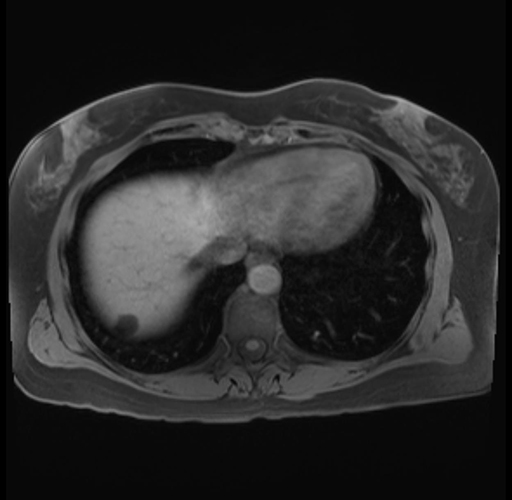

Imaging Analysis

Look through the patient's CT scan to identify any areas of concern for the necessary procedure.

Based on your CT findings, which issue(s) are present and would give reason for "planned slowing down moment(s)" in this case?